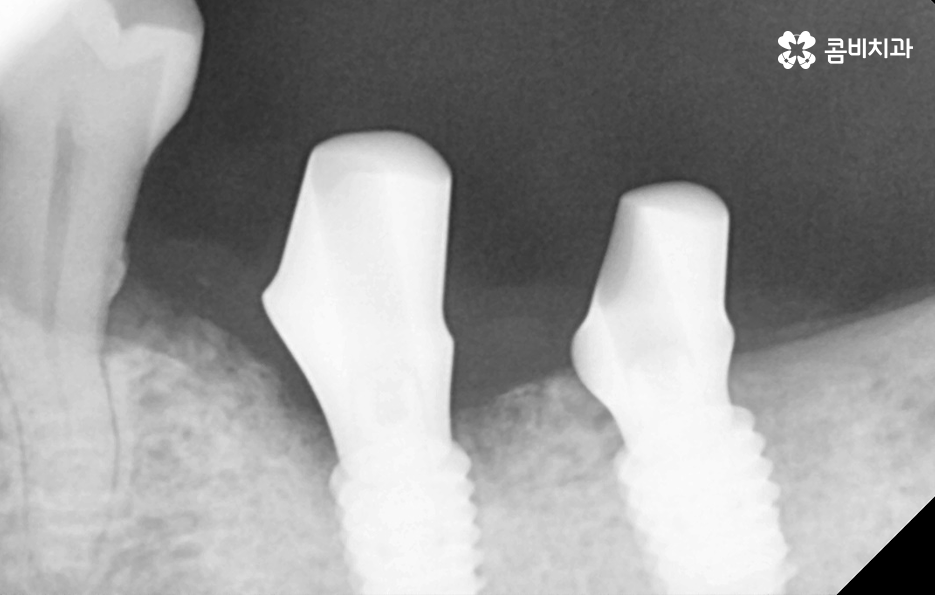

임플란트의 치료 원리를 살펴보면 임플란트는 잇몸 뼈에 심고 골 유착 과정을 통해서 저작력을 얻기 때문에 치료 전과 치료 후 모두 잇몸 상태가 매우 중요한 치료라는 것을 알 수 있어요

잇몸 뼈가 부족한 경우 뼈이식을 통해 임플란트를 식립하기 좋은 잇몸 상태를 만드는 것이 치료 결과에도 중요하며 임플란트의 식립 위치부터 각도, 깊이 등은 치과의 첨단 장비뿐 아니라 치과의사의 경험과 실력이 중요한 부분이기 때문에 임플란트의 전체 과정을 고려하여 비용도 중요하지만 건강한 치료 결과를 위해 종합적으로 따져보고 치과를 선택하시길 권하고 있어요